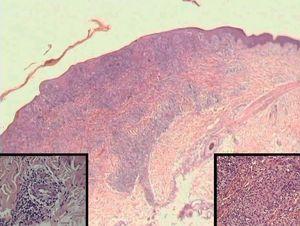

La histología mostraba leve paraqueratosis, con focos de neutrófilos formando costra, abundantes queratinocitos necróticos y un intenso infiltrado inflamatorio, que afectaba a las dermis superficial y profunda. El infiltrado era linfohistiocitario, con acentuación perivascular y presencia de células plasmáticas, produciendo cambios vacuolares basales y escasos focos de espongiosis (fig. 3). Se identificaba tumefacción endotelial en la dermis superficial y ocasionales fenómenos vasculíticos.

Fig. 3.--En la visión panorámica, a pequeño aumento se aprecia un infiltrado inflamatorio en la interfase y en la dermis profunda (Hematoxilina-eosina, x10). Detalle a la izquierda de un endotelio tumefacto con un infiltrado inflamatorio perivascular linfoplasmocitario (H-E, x40). A la derecha se aprecia una lesión granulomatosa en la dermis (H-E, x40).